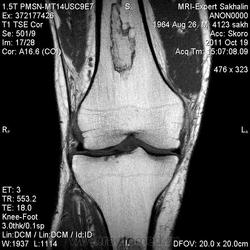

Мужчина с жалобами на боль в коленном суставе.Пришел сразу к нам по направлению врача с подозрением на ДОА, подагрический артрит.Рентгенограмм нет.

- В ранней стадии заболевания - отек (гипоинтенсивный на Т1-взвешенном изображении и гиперинтенсивный на Т2-взвешенном изображении)

- Позднее отграничение вдоль периферии пораженной кости (гипоинтенсивное на Т1 - взвешенном изображении; на Т2-взвешенном изображении - гиперинтенсивная линия по направлению к зоне некроза, соответствует грануляционной ткани)

- Гипоинтенсивная линия по направлению к здоровой кости (склероз, фиброз): признак двойной линии

- Накопление контрастного вещества периферической зоной

- При застарелых инфарктах кости интенсивность сигнала зоны некроза эквивалентна жировой ткани

- Периферическая зона типично извилистая, напоминает гирлянду.

а, b Инфаркт зрелого костного мозга. (а) Сагиттальная протонная плотно-взвешенная МРТ с подавлением МР-сигнала от жировой ткани. Изображение демонстрирует гирляндовидный склеротический край и центральный участок с сигналом жирового костного мозга. Множественные некротические зоны расположены преимущественно в метадиафизальной области, однако несколько находятся непосредственно рядом с суставом, в связи с чем имеется риск уплощения суставных поверхностей;